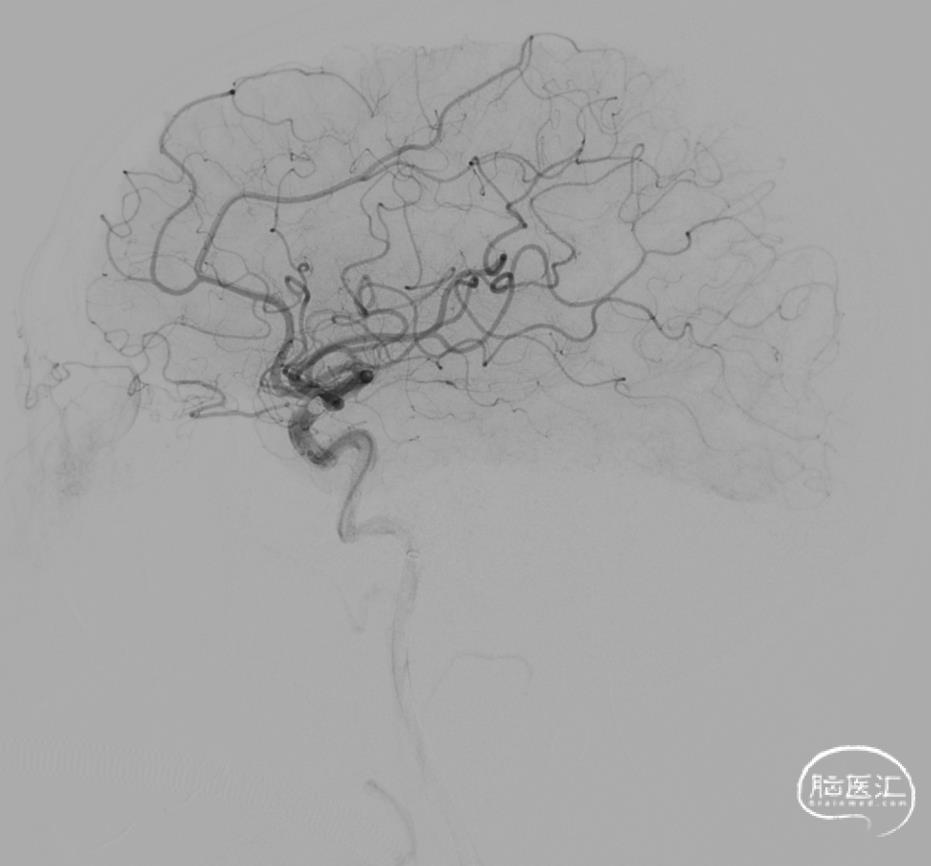

弓上造影:II型弓

超选右侧ICA正位及侧位造影

3D-RA成像

动脉瘤位于M1分叉处,三分支。